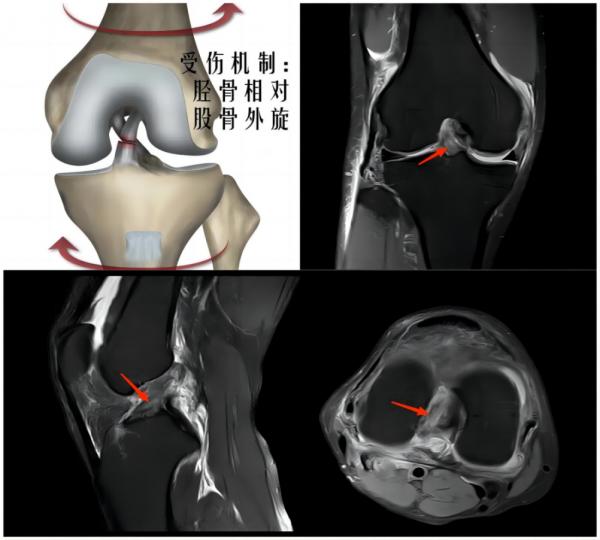

(上图为右膝前交叉韧带撕裂)

常见原因:足球运动中时常发生高频次的急停、冲刺、变向等,并且还会有膝关节的屈伸、外展等动作,这些动作都会增加对膝关节的负荷,从而引发膝关节损伤。主要损伤为半月板体部撕裂、半月板根部撕裂、侧副韧带及交叉韧带的扭伤或撕裂。